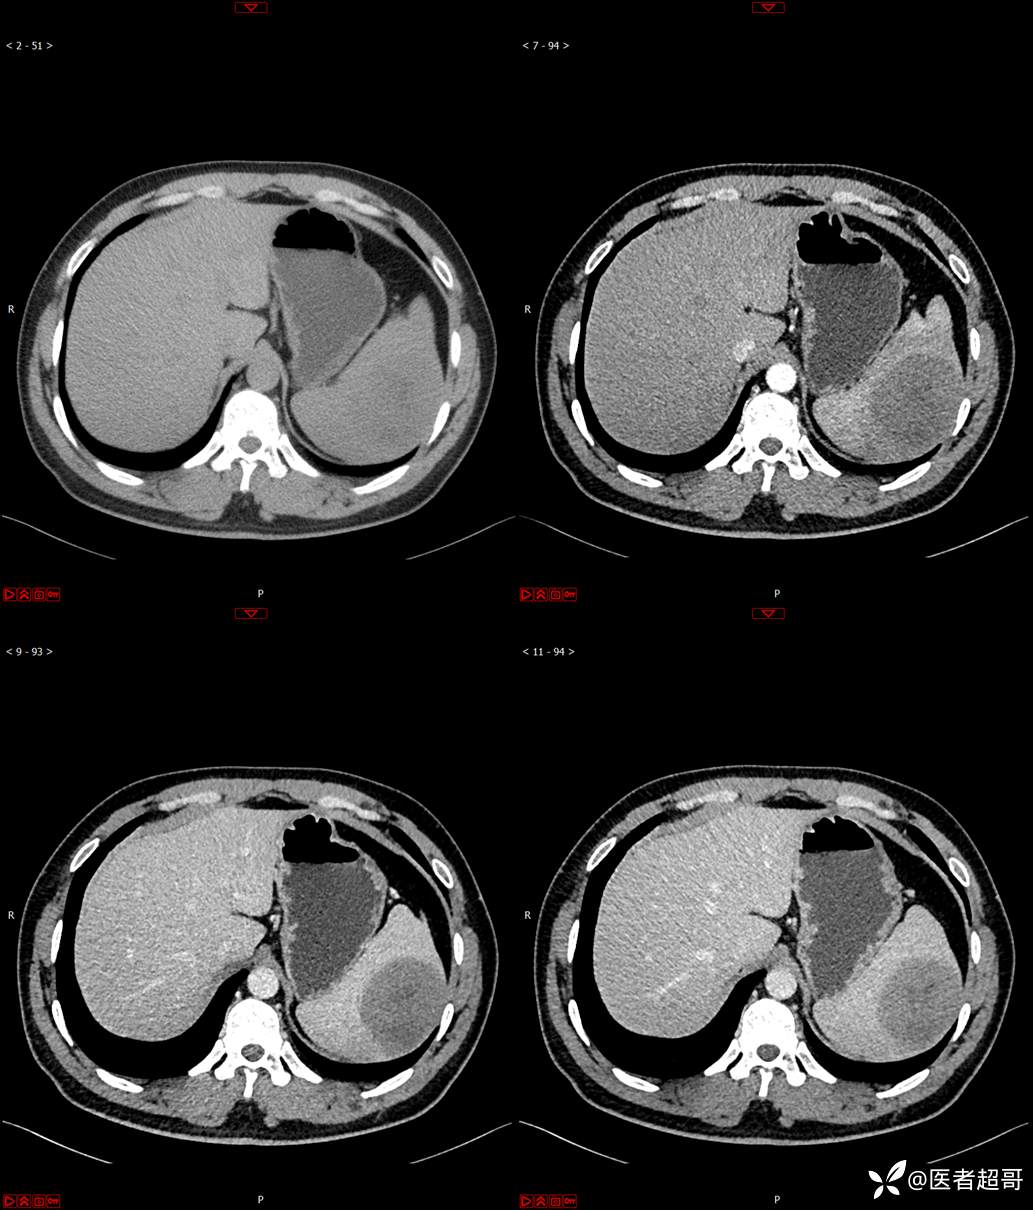

【影诊笔记596】脾脏占位01,你的病谱能网住吗?请分析,留言查询病理及术程!

主 诉:发现脾占位2月余。

现病史:患者2月余前体检彩超提示脾占位性病变,未予特殊诊治,2023.12.1于潍坊市坊子区人民医院行肝胆胰脾MR平扫提示脾脏占位性病变,左肾小囊肿,现患者无腹胀、腹泻,无恶心呕吐,无胸闷憋气等症状,今为求进一步治疗,患者来我院就诊,门诊以“脾占位性病变”收入院。患者自发病以来,一般情况可,神志清,精神可,饮食、二便正常,睡眠可,体重体力无明显改变。